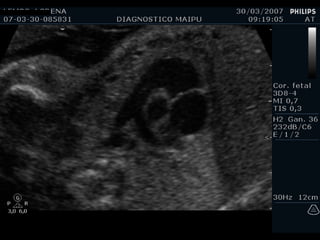

EXAMEN BASICO GENERAL Ubicación Eje Tamaño  Cámaras Pericardio Ritmo VALVULAS AV Apertura y movimiento Inserción AURICULAS Tamaños Flap del foramen oval Septum VENTRICULOS Tamaños Paredes Banda moderadora Tabique

EXAMEN BASICO GENERAL Ubicación Eje Tamaño  Cámaras Pericardio Ritmo

Ubicación

Eje

Tamaño

Cámaras COLUMNA AORTA ESTERNON VP VP BANDA MODERADORA FLAP VI VD AI AD